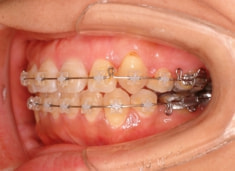

治療後(2年5ヶ月後)